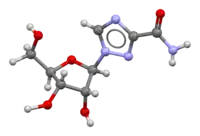

Treatment

In-depth research into Lujo virus and its treatment have been difficult because of the lack of economic and cultural stability of the regions where the only known cases have occurred. Under Treatment with oral ribavirin treatment, the patient 5 continued to deteriorate but the treatment shifted to i.v on day 8 it seemed to have cured the only surviving patient with Lujo Virus, but because the 5 affected in 2008 have been the only cases identified, there has not been much opportunity for further research.[16][12]